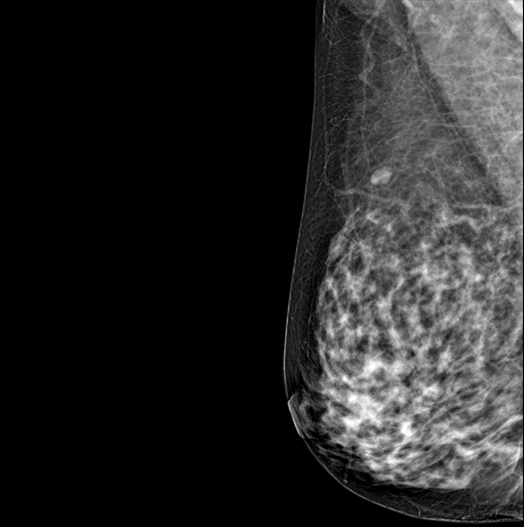

SYNTHESIZED 2D

HESTIA supports "Synthetic 2D" that generates 2D images only by tomography shooting without additional 2D shooting.